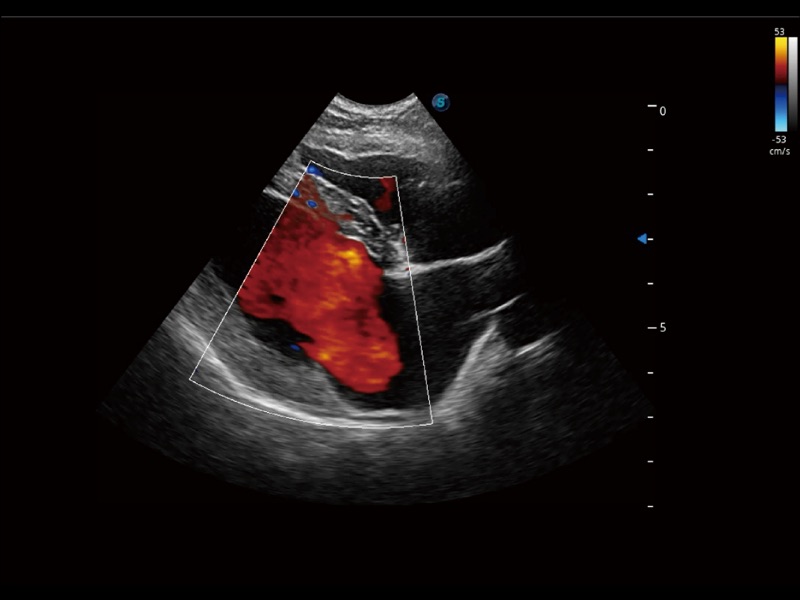

通過創(chuàng)新的 Matrix E自適應(yīng)濾波器和超長時間域算法,極大提升超低速微細(xì)血流的檢出能力,同時更精準(zhǔn)地濾除軟組織和噪聲信號,為獸用醫(yī)生提供以往無法通過常規(guī)血流獲得的疾病診斷信息。